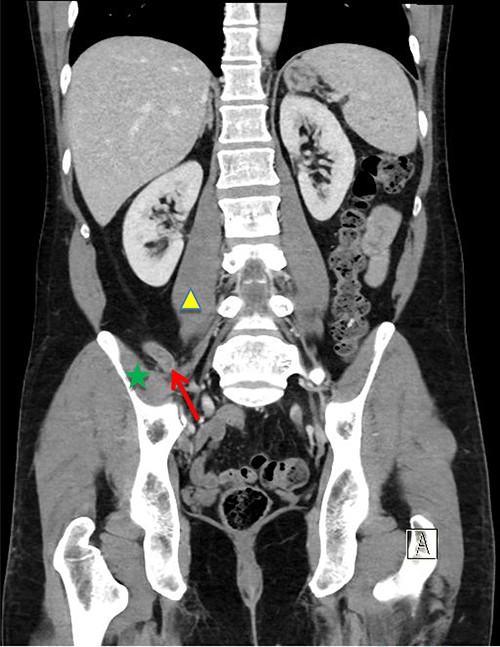

The patient was re-admitted and examination revealed a soft abdomen with localized rebound tenderness in the right iliac fossa. A computed tomography (CT) abdomen was requested and a referral made to the surgical team. The CT scan illustrated AA with the appendix located posterior to the ileo-psoas muscle (Figs 1–3). A diagnostic laparoscopy was performed, which revealed the head of the inflamed appendix herniated posterior to the psoas muscle in a cavity, (~25 mm deep and 10 mm in diameter) that could not be dissected laparoscopically (Fig. 2). Therefore, an uncomplicated open appendectomy was performed and the patient was admitted for post-operative observation. Recovery was uneventful and the patient was discharged without follow-up.

Coronal CT image. Inflamed appendix (red arrow) positioned between psoas (yellow triangle) and iliacus muscles (green star).